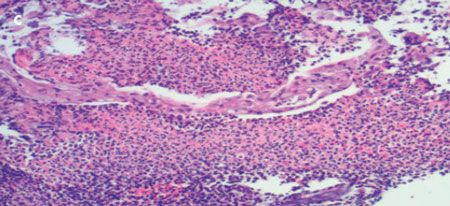

The patient had tenderness in the right upper quadrant, without signs of peritonism. A CT scan with contrast of the abdomen and pelvis demonstrated an apple core lesion (A). Colonoscopy revealed an ulcerated mass in the ascending colon, which strongly suggested malignancy (B). However, a biopsy specimen of the lesion showed only inflammatory changes with areas of ulceration (C).

It is becoming increasingly clear that NSAIDs, including salicylates, may adversely affect the colon as well as the upper GI tract.1,2 They may cause nonspecific colitis or exacerbate a preexisting colonic disease. Presenting features include abdominal pain, weight loss, diarrhea (bloody or nonbloody), and iron deficiency anemia. Colonoscopy may show inflammation, ulceration, or stricture. Histology often shows a nonspecific colitis or pattern similar to that of ischemic colitis.3